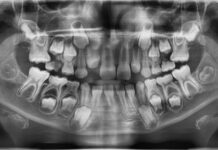

Ritengo innanzitutto che sia preziosa in apertura la presenza del presidente CAO dell'Ordine dei Medici di Varese Stefano Casiraghi e del direttore del Dental center di Humanitas Roberto Weinstein. Già questo è l’indice di una visione olistica, che è quella che appunto vogliamo adottare. Si parlerà poi di come il proliferare di 800 specie batteriche nel cavo orale, aggressive a livello sistemico, perché mutate, possa incidere sull’oncogenesi, o sullo sviluppo di Alzheimer e demenza senile. Alcuni ceppi batterici possono giocare un ruolo importante nell’indurre tumori del pancreas e della mammella, oltre a disturbi e patologie cardiologici e cancro della bocca. Paragoniamo il cavo orale all’Amazzonia, per patrimonio di biodiversità; e l’intestino alla Cina, per numero di batteri. La fotodinamica e il controllo delle citochine rappresentano, inoltre, ulteriori materiali di riflessione.